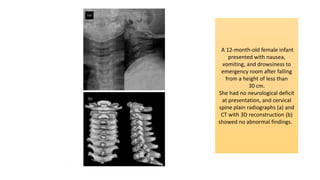

A 12-month-old female infant

presented with nausea,

vomiting, and drowsiness to

emergency room after falling

from a height of less than

30 cm.

She had no neurological deficit

at presentation, and cervical

spine plain radiographs (a) and

CT with 3D reconstruction (b)

showed no abnormal findings.